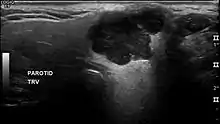

يعمل تشخيص أورام الغدد اللعابية على استخدام عينات من الأنسجة بالإضافة إلى دراسة صور الأشعة. إجراءات أخد عينات من الأنسجة تشمل الشفط بالإبرة النحيفة و خزعة الإبرة المركزية (إبرة أكبر من الإبرة النحيفة الشافطة). كلا الإجرائين السابقين يمكن القيام بهما خارج المستشفى. تقنيات التصوير التشخيصية لأورام الغدة اللعابية تتضمن الموجات فوق الصوتية ، التصوير الطبقي المحوسب، الرنين المغناطيسي . يمكن لخزعة الشفط بالإبرة النحيفة إذا أجراها أطباء مختصون أن تحدد ما إذا كان الورم خبيثاً بطبيعته بدرجة حساسية تصل إلى حوالي ال90% .[1][2] ويمكن أيضاً لهذه التقنية التفريق بين ورم الغدة اللعابية الأولي وبين الورم الذي يحمل قابلية للانتشار . خزعة الإبرة المركزية يمكن أن يتم إجرائها دون الحاجة لإدخال المريض إلى المستشفى . هذه الطريقة أكثر امتدادا واجتياحاً لكنها أكثر دقة مقارنة بسابقتها مع درجة حساسية تفوق ال97%،[3] بالإضافة إلى أن هذه التقنية تسمح بطباعة نسيجية أكثر دقة للورم . فيما يخص الدراسات التصويرية، تقنية الموجات فوق الصوتية يمكن ان تحدد وتشخص أورام الغدة النكفية. بعض أورام الغدة اللعابية تحتوي على خصائص تخطيطية خاصة في الموجات فوق الصوتية.[4] وتستخدم هذه التقنية أيضاً لتوجيه نوعي الخزعات السابق ذكرها : خزعة الشفط بالإبرة النحيفة وخزعة الإبرة المركزية. يسمح التصوير الطبقي المحوسب برؤية مباشرة وثنائية الجانب لورم الغدة اللعابية وتوفر معلومات عن الأبعاد الكلية للورم والانتشار داخل الانسجة. يعتبر التصوير الطبقي المحوسب تقنية ممتازة لعرض الانتشار واللاجتياح في العظم. يقدم الرنين المغناطيسي تخطيط أفضل للأنسجة الرخوة فقط مقارنةَ بالتصوير الطبقي كمعرفة الغزو حول العصب .[5]